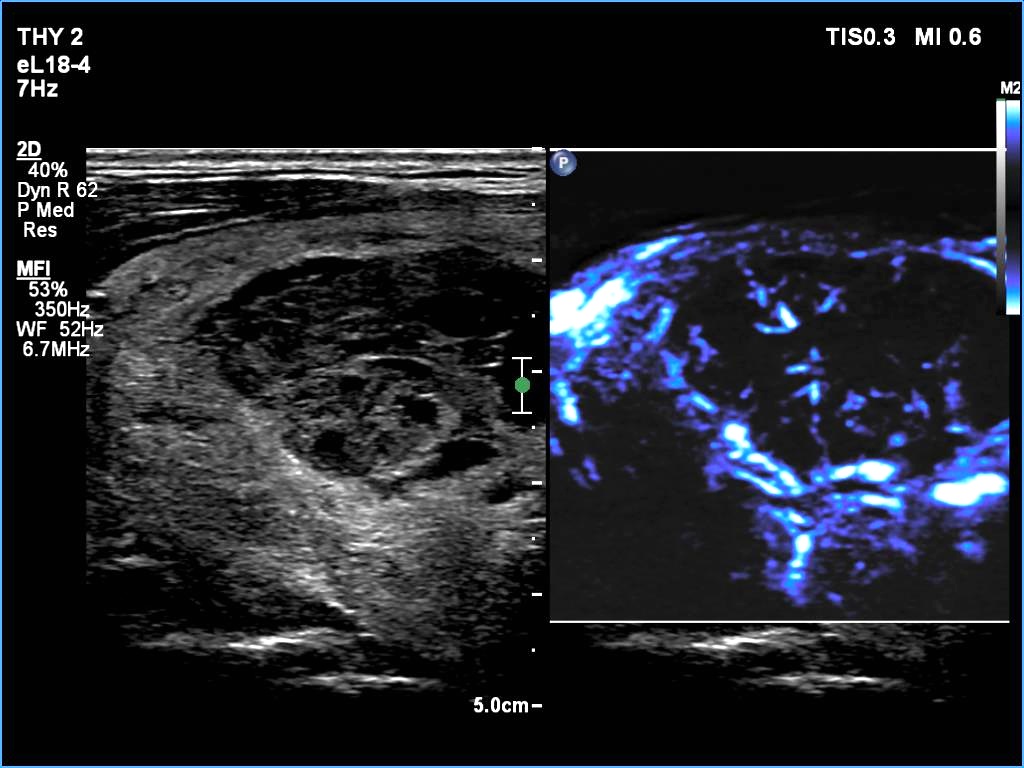

Ultrasonography: The thyroid was echonormal. There was a larger nodular mass in the right lobe which was composed of a dominantly solid echonormal portion that surrounded a dominantly cystic area. There were multiple nodules in the left lobe. The latter included an almost completely cystic lesion.

Comment. The right nodule is dominantly solid one because the cystic portion is less than 50%. The cystic portion of the nodule is multichambered which presents spongiform areas. The left cystic nodule is an almost completely cystic lesion, that has disappeared after the removal of cystic fluid.